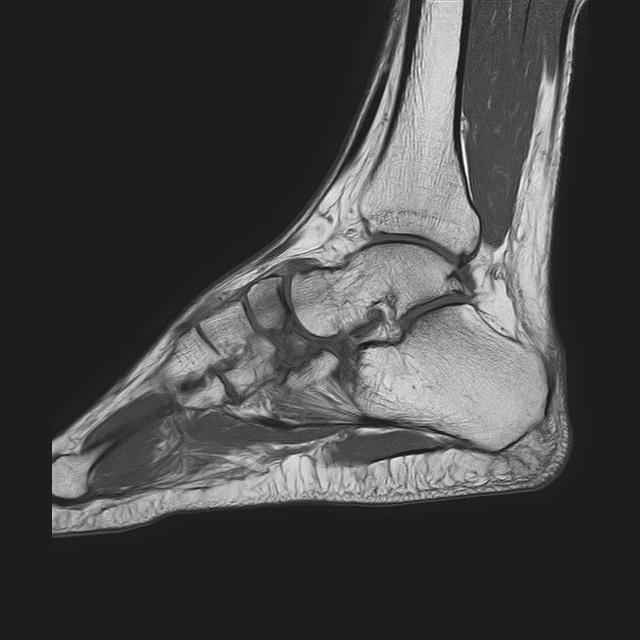

Дорогие коллеги,Мужчина 36 лет, пострадал около 8 месяцев назад в ДТП (водитель мотоцикла).

Подтаранный вывих лечили гипсовой лонгетой. Недиагностированным остался перелом ладьевидной кости, который беспокоит в настоящее время. Аваскулярный некроз кости, похоже. Добавил наиболее значимые снимки, на мой взгляд.

По данным снимкам однозначно сказать о некрозе ладьевидной кости нельзя. Типичные изменения при аваскулярном некрозе ладьевидной кости, как правило, начинаются в центральной её части с дальнейшим развитием коллапса. В данном случае в значительной степени пострадал таранно-ладьевидный сустав, вероятнее всего, именно это является причиной болевого синдрома. При отсутствии эффекта от физиотерапии и ношения ортопедической обуви в течение ближайших 6 месяцев придётся ставить вопрос о таранно-ладьевидном артродезе.